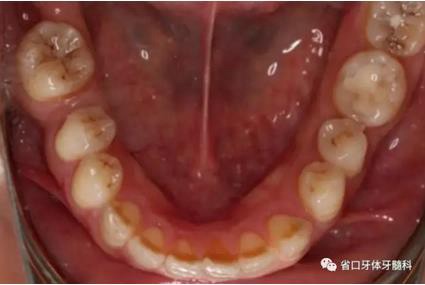

1.?病例簡介 43歲女性患者,主拆:右上前牙松動(dòng)不適數(shù)日要求修復(fù)?,F(xiàn)病史:患者數(shù)年前右上前牙因“齲壞”于外院行根管治療(具體不詳),數(shù)日前牙冠松動(dòng)不適,現(xiàn)覺影響咀嚼及美觀,遂來我院要求進(jìn)一步診治。否認(rèn)高血壓、心臟病等重大疾病,否認(rèn)結(jié)核、肝炎等傳染病史,否認(rèn)手 術(shù)、輸血史等,未發(fā)現(xiàn)藥物過敏。無吸煙習(xí)慣。臨床檢查:口外觀顏面基 本對稱,皮膚無紅腫破潰,顳下頜關(guān)節(jié)區(qū)無彈響、雜音、壓痛,開口度約 37mm,開口型“↓”,頜下、刻下和頸部未及腫大淋巴結(jié)。中位笑線??趦?nèi)檢查,口腔衛(wèi)生可,色素(+),BOP(-),PD=2mm,上頜右側(cè)中切 牙冠部變色,冠根折斷至齦下3mm,叩不適,松動(dòng)Ⅱ°~Ⅲ°。牙齦稍紅, 齦緣水平及齦乳頭高度可,屬于中厚齦生物型,附著齦寬度約5mm,唇系帶附著可。上頜右側(cè)中切牙缺牙間隙與對側(cè)同名牙一致,約>7mm,修復(fù)空 間良好。與對頜牙覆合覆蓋正常。MCT檢查示上頜右側(cè)中切牙冠根折斷至骨 下,根管內(nèi)見充填物,根充不全,根尖見陰影,大小約3mm×3mm。牙槽窩根方可用骨量可,唇側(cè)骨壁完整,冠方骨壁厚度約1mm。

圖1 術(shù)前口內(nèi)照

圖2 術(shù)前口內(nèi)照

圖3 術(shù)前口內(nèi)照